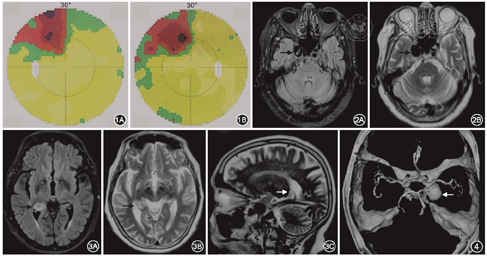

患者女性,82岁。因视物重影5个月,于2017年12月4日至北京协和医院就诊。患者5个月前无明显诱因出现视物重影,伴右侧额面部轻微痛觉,否认视力下降,无恶心、呕吐、耳聋、耳鸣,无语言及吞咽障碍,无肢体感觉及运动障碍,无自主神经功能障碍。既往高血压病史30年,最高血压(高压/低压)202/91 mmHg(1 mmHg=0.133 kPa),平时控制在160/70 mmHg左右;冠心病10余年,现冠心病二级预防治疗中。眼部检查:右眼外转绝对受限。视野示右眼鼻上象限、左眼颞上象限局部视野缺损,伴黄斑回避(图1)。头部核磁共振平扫示右侧海绵窦旁类圆形流空影(图2),提示右侧颈内动脉海绵窦段动脉瘤;右侧海马后部异常信号(图3),建议进一步增强检查;双侧额顶叶、双侧侧脑室旁、基底节区及桥脑多发异常信号,慢性缺血性改变可能。计划入院进一步行头部血管检查。入院后眼部检查:矫正视力右眼为0.5,左眼为0.6;眼压右眼为14 mmHg,左眼为14 mmHg;右眼显性内斜,左眼正位。右眼外转受限,左眼各方向运动无明显受限。双眼睑无水肿、下垂。双眼结膜无明显充血,角膜透明,无角膜后沉着物,前房深度正常,房水清,虹膜纹理清,无前后粘连。双眼瞳孔等大同圆,对光反射灵敏,相对性瞳孔传入障碍(-)。双眼人工晶状体在位。双眼玻璃体轻度混浊。双眼视盘边界清晰,颜色淡红,血管走行大致正常,视网膜在位,未见出血、渗出,双眼黄斑区色素紊乱。入院后为进一步确诊,行头颈CT血管造影容积再现检查,结果显示右侧颈内动脉虹吸段动脉瘤,大小约15 mm×19 mm(图4);头颈部动脉多发粥样硬化改变伴部分血管狭窄;双侧额顶叶、侧脑室旁、基底节区及脑桥多发稍低密度影,缺血改变可能。因而患者主诊断为右侧颈内动脉海绵窦段大动脉瘤,右侧展神经麻痹。患者于2017年12月29日全身麻醉下行数字减影血管造影检查(图5中A),见右侧颈内动脉虹吸段一动脉瘤,大小约20 mm×17 mm,动脉瘤远端颈内动脉床突段局部狭窄,狭窄约80%,左椎动脉起始部狭窄约70%,基底动脉局部狭窄约90%。遂同时行支架辅助动脉瘤栓塞术,术后再次造影示动脉瘤栓塞完全,颈内动脉血流顺畅(图5中B)。术后1周患者右侧面部感觉有好转,但右眼外转受限无明显改善。术后6个月随访,患者临床情况稳定,右眼外转受限仍无明显改善,视野表现大致同前。

本例患者的特别之处还在于双眼上象限同向非一致性局部视野缺损,伴黄斑回避。同侧的视野缺损见于外侧膝状体后的视路病变,而同侧上象限视野缺损可见于颞叶病变。视路的神经纤维离开外侧膝状体后形成视放射,视放射的腹侧束先向前外方走向颞叶,在视交叉平面,绕过侧脑室下角前端的上方行至其外壁,沿侧脑室颞角形成Meyer襻,终止于枕叶皮质纹状区。Meyer襻损伤可引起病灶对侧的同向上象限非一致性视野缺损,并且有黄斑回避。导致Meyer襻损伤的病因主要为颞叶、海马、杏仁核区的病灶或这些部位外科手术损伤,如癫痫患者的颞叶切除手术。仔细回顾患者的病史及检查结果,发现患者的海马后部异常信号有部分突入侧脑室颞角,压迫侧脑室颞角,因此患者的视野缺损是由视放射Meyer襻损伤导致的典型改变。